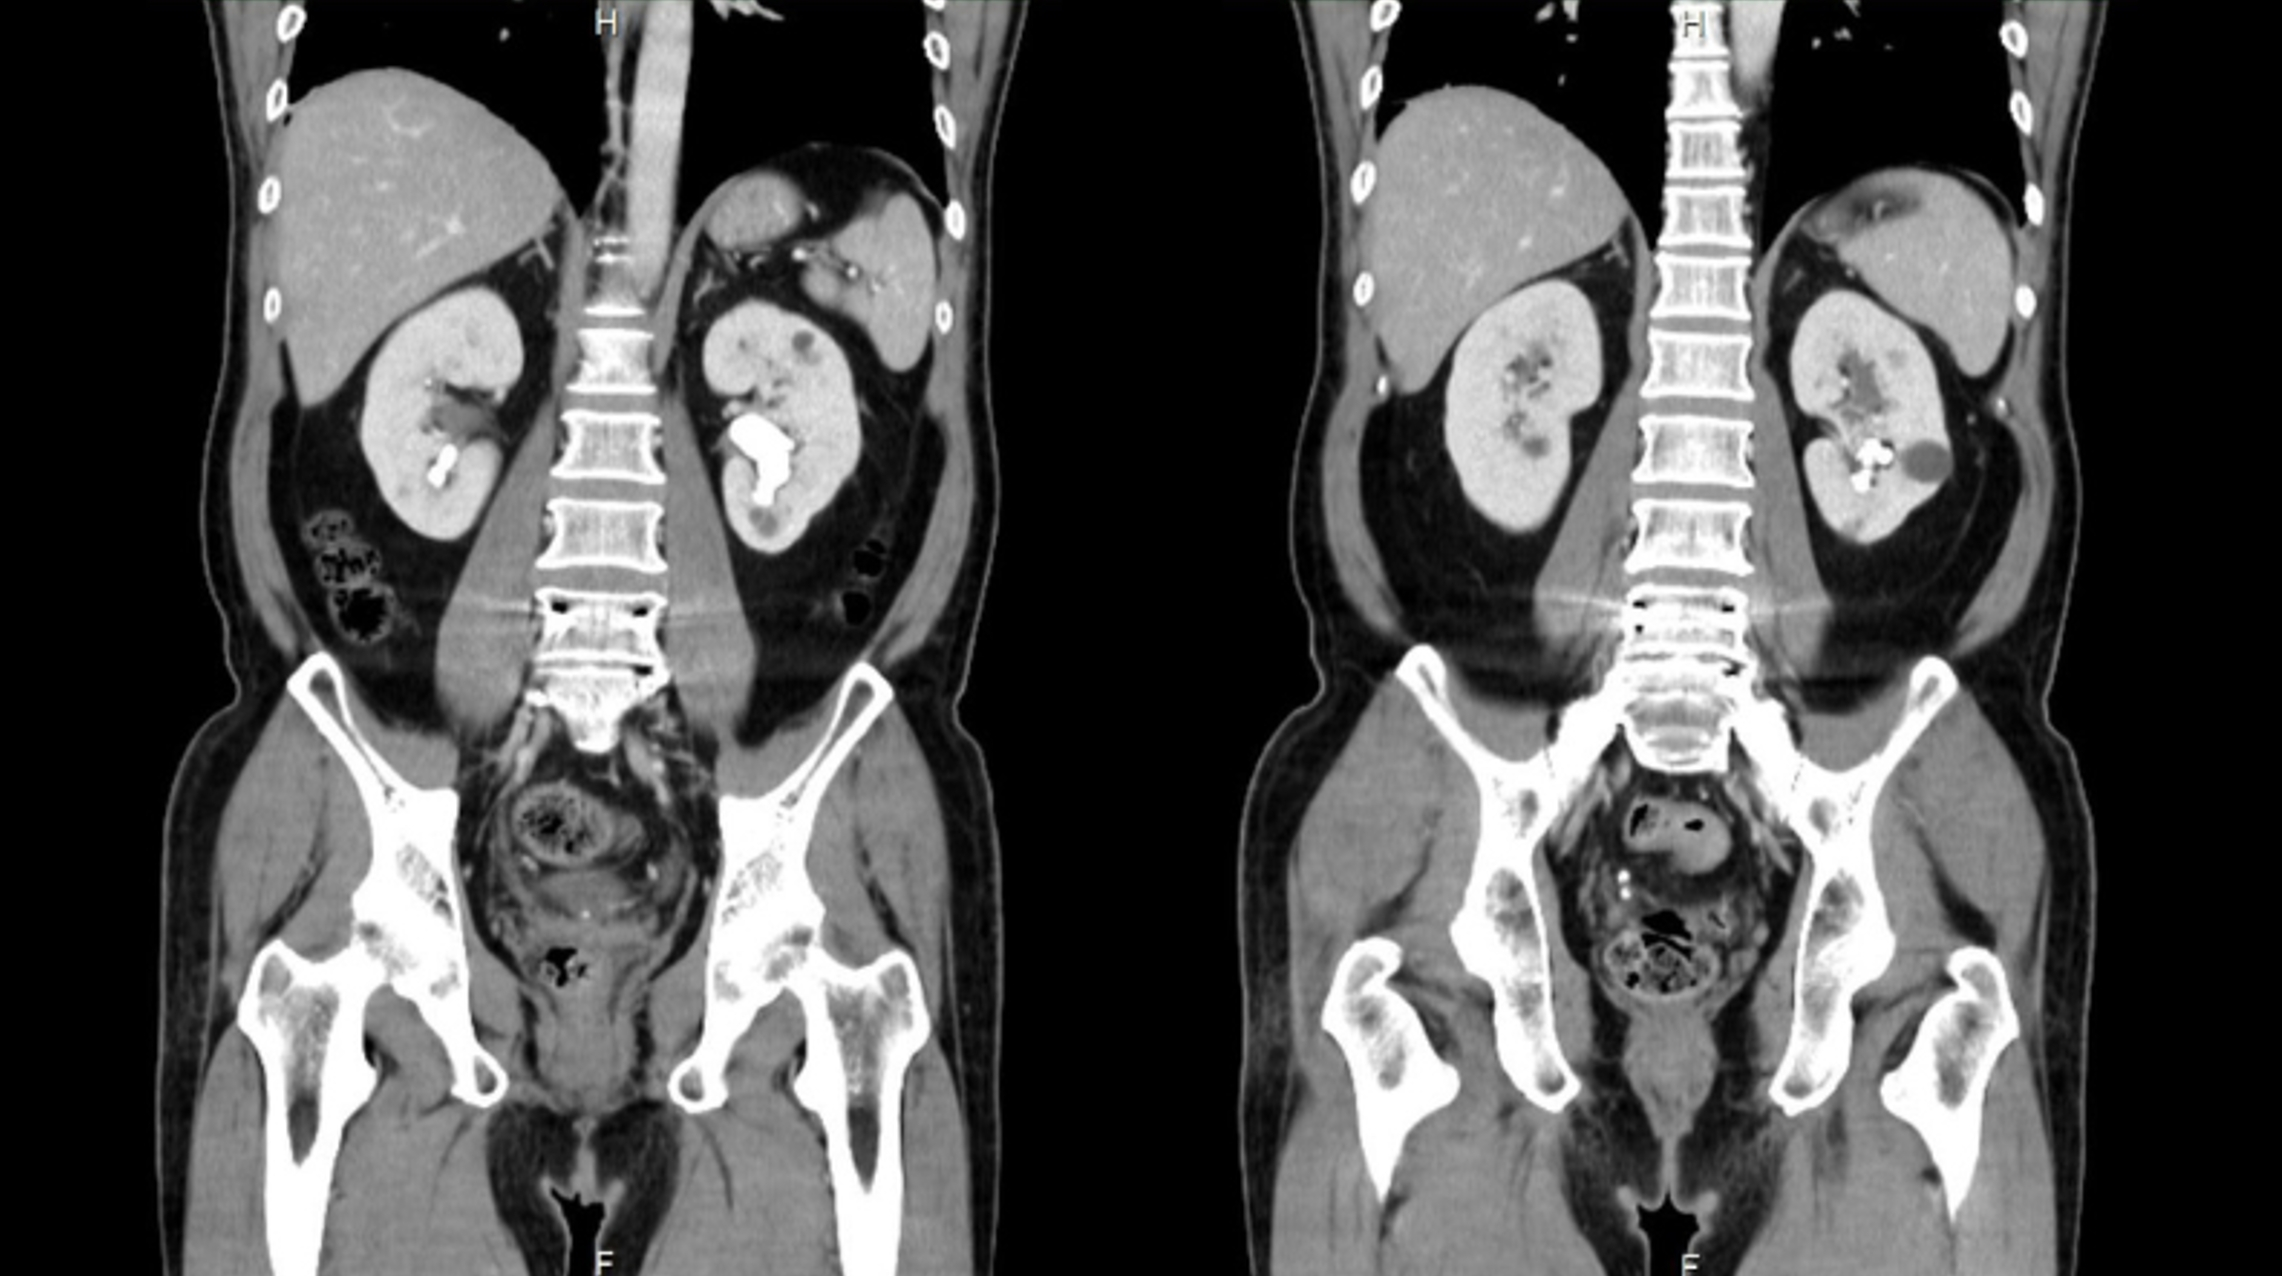

經衛福部雙和醫院泌尿科董劭偉醫師檢查發現,其病情較為複雜屬於複雜型腎結石,雙側腎臟皆有結石,尤其左側腎臟為最長徑達3公分的「部分鹿角結石」並延伸至下腎盞,右側同樣有下腎盞結石。楊先生擔心傳統手術傷口大且恢復期長會影響工作,遲遲不敢手術,董醫師醫病溝通後,決定採用「新世代微創金三角」技術治療,楊先生術後全身無傷口,成功清除雙側腎結石,且隔日順利出院,重返職場恢復日常生活工作。

董劭偉醫師解釋,像楊先生左側最長達 3 公分的「部分鹿角結石」被視為手術的大魔王,因其結石分支延伸至不同腎盞,尤其下腎盞位於腎臟最底部,角度非常刁鑽。一般使用「經皮穿腎取石術需在背部穿孔,若要清除乾淨楊先生的鹿角結石過去往往可能需多處穿刺,出血風險與術後疼痛對患者壓力較大。更重要的是,傳統治療後患者還需自行排石,而結石復發的主因往往在於術後殘留的微小碎屑,若僅靠人體自然排出,未排淨的碎片極易成為新結石生成的種子。因此,本次治療董醫師以 7.5Fr. 極細軟式輸尿管鏡由天然尿路進入,無須開刀,配合吸石清負壓可彎式導管鞘的技術,將碎片、粉末吸出體外,對於多發性及下腎盞結石有助於達到更高的清除率,減少未來復發機率。